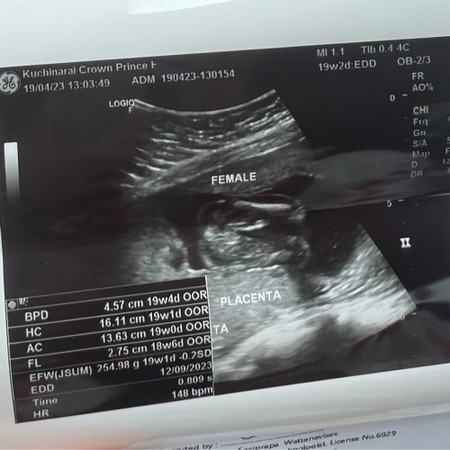

ท้องได้ 20 Week เพศน้อง

ท้องได้ 20 week ตอนซาวน์คุณหมอบอกว่าได้ลูกสาว แม่ๆคิดว่าอนาคตน้องจะมีจู๋โผล่มามั้ยคะ พอดีบ้านนี้อยากได้ลูกสาว เเต่กลัวดีใจเก้อค่ะ🥹😂 บางคนก็บอก พอ25-30 week+ จะเห็นชัดกว่านี้น้องอาจจะมีจู๋ก็ได้ เเม่นี่คิดหนักเลยค่ะ 😄😄

เราว่าลูกสาวนะคะ เห็นเป็นกลีบๆ แต่ถ้าไม่แน่ใจ รอบหน้าซาวด์อีกรอบดูค่ะ

ตอนซาวน์เพศครั้งเเรก 16w น้องยังไม่ถ่างขา คุณหมอให้ไปทางผญ70% พอนัดไปอีกรอบ 19wกว่าๆ คุณหมอบอกผญค่ะ ผู้ใหญ่เเถวบ้านบอกอย่าพึ่งดีใจ บางคนคลอดมาเป็นผช ก็มี เค้าเลยกลัวดีใจเก้อค่ะเเม่

ลูกเราก็โชว์แบบนี้ค่ะหมอบอกผู้หญิง ไม่มีอะไรโผล่ออก